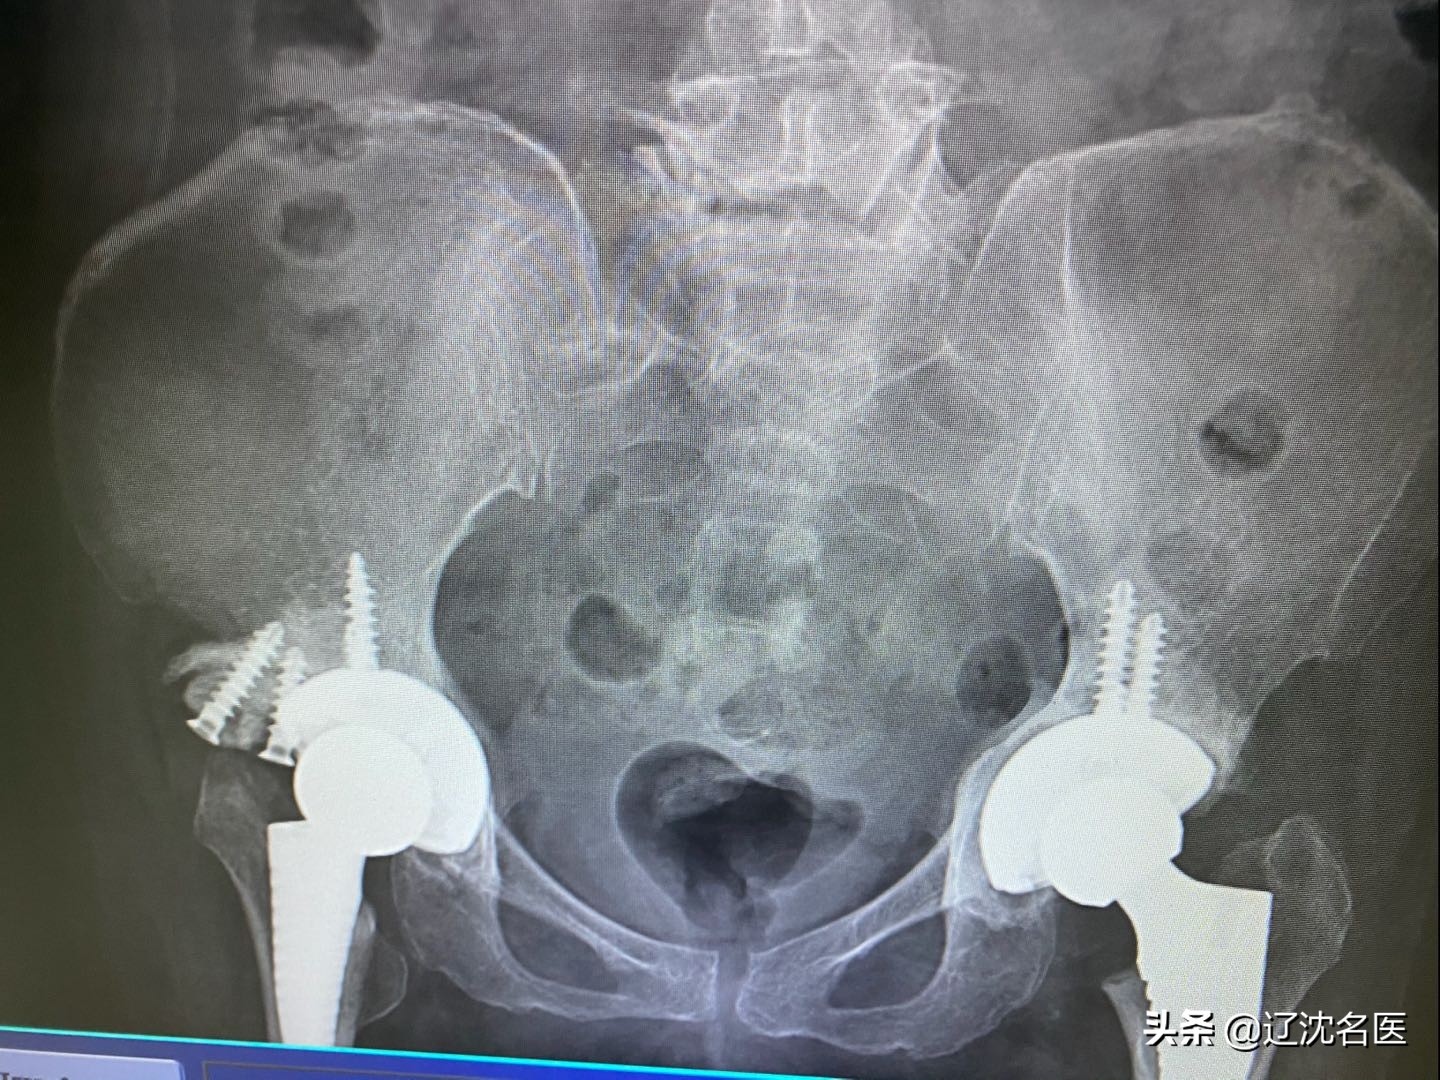

手术方法上,医生采用了3D打印技术,精准复原病变骨盆模型,成功为她置换了双侧关节;

同时,为确保手术安全顺利,骨科病房再度应用3D打印技术,与第三方合作,在放射线杨丽萍主任的配合下,成功打印出范女士的骨盆3D模型,结合模型科内医生又进一步的讨论,制定了详细的手术方案。

2019年10月24日,宋长福主任、陈阳医生、段野医生协作,为范女士实行了同期双侧全关节置换术。手术过程非常顺利,不但缩短了手术时间,还实现了精准治疗,术后的范女士恢复十分满意,能够正常站立行走!